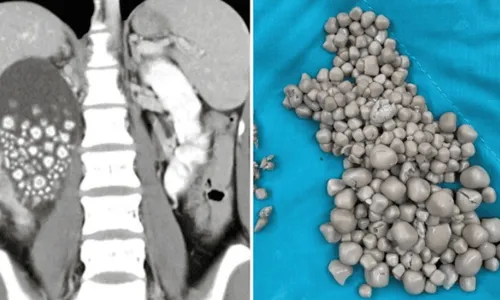

Mais de 300 pedras

Imagem ilustrativa da imagem Pedra nos rins atinge cada vez mais crianças, diz médico

Pedras nos ris de jovem |  Foto: Divulgação

Uma jovem de 20 anos retirou mais de 300 pedras do rim em hospital de Taiwan. Segundo os médicos do Centro Médico Chi Mei em Tainan, na região sul de Taiwan, a mulher não gostava de tomar água e se hidratava, há anos, com chás açucarados, suco de frutas e bebidas alcoólicas.

A mulher procurou ajuda médica após ter febre intensa e dores na região da cintura. As pedras retiradas, por meio de uma cirurgia, variavam entre 0,5 e 2 centímetros.